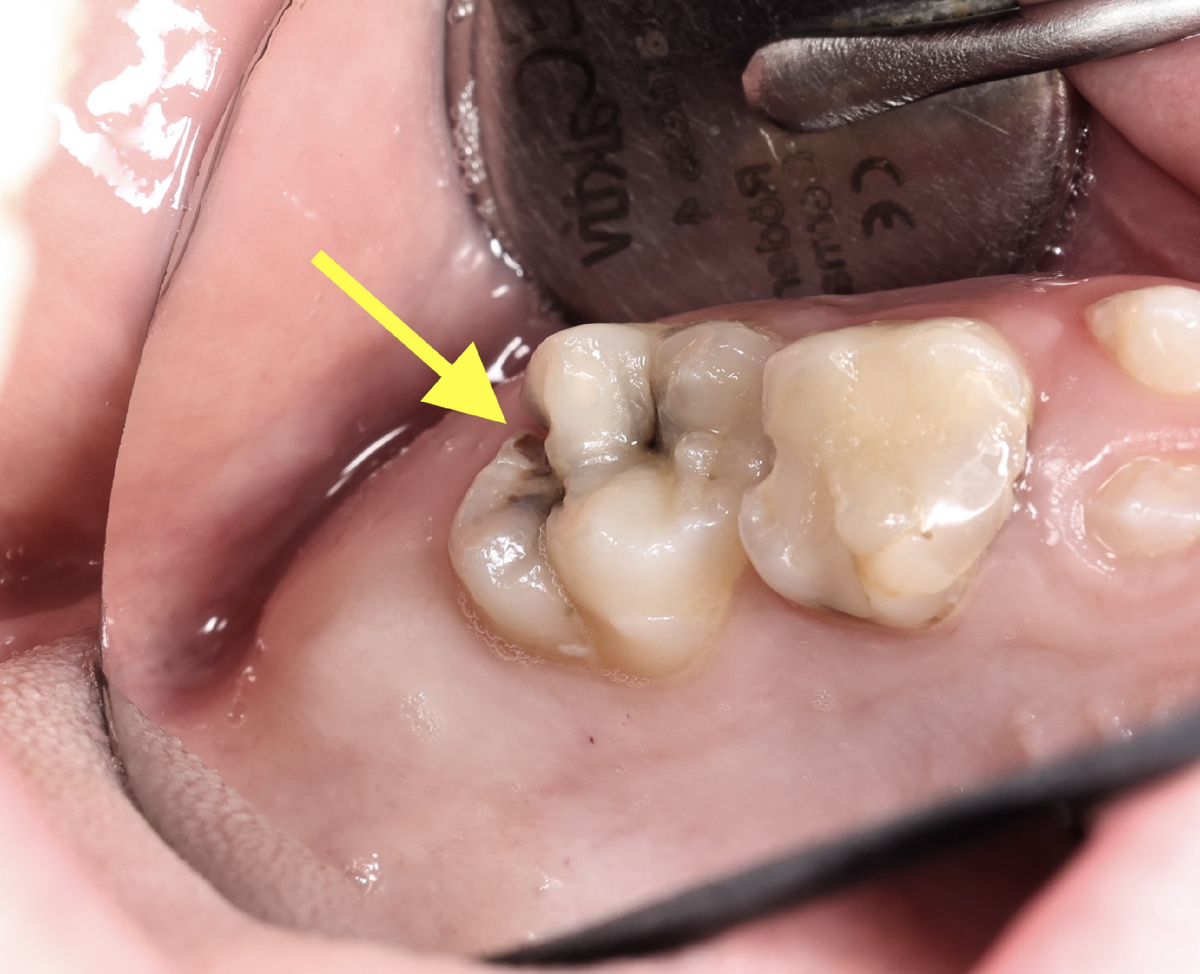

Вообще, не каждый сможет понять самостоятельно, что зуб в большой опасности находится:

Кариес

Начали "сверлить":

Удалена часть тканей